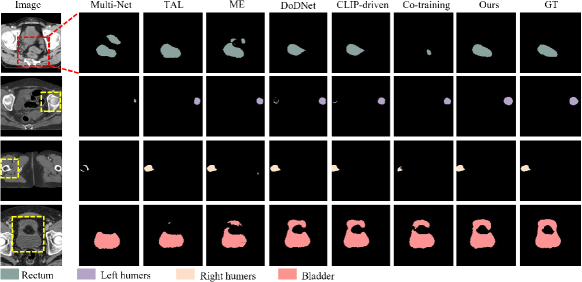

Tables I, II, III and IV present the segmentation results for the head and neck, chest, abdomen, and pelvis, respectively. Figs. 4, 5, 6 and 7 provide visualizations of these methods. The following conclusions can be drawn from these results:

Unified segmentation models generally outperform Multi-Net, as indicated by combined DSC and ASSD metrics. Among channel adjustment methods, ME outperforms TAL by leveraging non-overlapping organ annotations across datasets. The conditionally-guided DoDNet achieves sub-optimal results in the chest and abdomen but performs poorly in the head and neck and pelvis, particularly for the chiasm and parotid glands; The method also struggles to distinguish between symmetrical structures (e.g., parotid glands and humerus), as noted in COSST [4]. The CLIP-driven method performs poorly across all regions, especially for less frequent organs and structures like the chiasm. The Co-training method, based on two stage pseudo-labeling, achieves competitive results, particularly in the pelvis. Overall, our method outperforms others across all regions, especially for small organs like the chiasm and elongated organs like the esophagus. Visually, our method aligns more closely with GT, avoiding the segmentation errors of channel adjustment and the issues with symmetric structures in conditional guidance methods.

The effectiveness of our method has been demonstrated through the experiments on diverse datasets encompassing the head and neck, chest, abdomen, and pelvis, which has consistently achieved superior performance in each of these regions, surpassing the state-of-the-art methods (see Tables I, II, III and IV). Additionally, visual results show that our method’s segmentation results closely matches the ground truths (see Figs. 4, 5, 6 and 7). According to the results obtained by different methods, incorporating organ-specific priors, as evidenced in TAL [8] and ME [9], and employing pseudo-labelling through Co-training [5], effectively enriches the supervisory signals, thereby enhancing segmentation outcomes. Conditional information-guided methods excel with specific organs but struggle with smaller structures, and they are unable to differentiate between symmetric structures, such as the left and right parotid glands and the left and right humers, as shown in the fifth column of Figs. 4 and 7. Although CLIP-driven method has achieved significant success in the segmentation of abdominal organs[12], it relies on large datasets for training, and most of the images pre-trained by CLIP are natural images. Therefore, further exploration is needed to adapt this method to medical imaging.